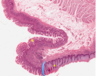

·gall bladder - no muscularis mucosa, submucosa, crypts

From the liver, bile obviously goes through those bile ductules into larger bile ducts that are found in the portal tracts out eventually to the gallbladder. Students confuse the gallbladder with the intestine, or the small intestine. So I’ve put some of the things that are not here, compared to the small intestine.

·There’s not going to be a muscularis mucosa, which you saw in intestine. There’s not going to be a separate submucosa, there’s not going to be crypts, although sometimes there’ll be downgrowths (1) called Aschoff sinuses that are abnormal. And the surface has folds, but these are not really villi.

·And, in addition, if you think about – you’ve seen the abdominal cavity, right? So you know the gallbladder’s smack up against the liver. The side that’s against the liver doesn’t have a mesothelium – it just has an adventitia, but the part that faces the abdominal cavity has a mesothelium out here, and this layer is called the serosa. Again, the complex folds on the surface are not villi. Make sure when you look at the gallbladder that you can distinguish it from the small intestine.